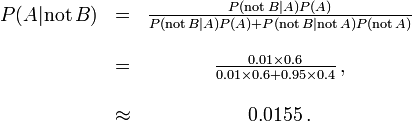

Let A represent the condition in which the patient has the disease, and B represent the evidence of a positive test result. Then, probability that the patient actually has the disease given the positive test result is

and hence the probability that a positive result is a false positive is about  , or 98%.

, or 98%.

Despite the apparent high accuracy of the test, the incidence of the disease is so low that the vast majority of patients who test positive do not have the disease. Nonetheless, the fraction of patients who test positive who do have the disease (.019) is 19 times the fraction of people who have not yet taken the test who have the disease (.001). Thus the test is not useless, and re-testing may improve the reliability of the result.

In order to reduce the problem of false positives, a test should be very accurate in reporting a negative result when the patient does not have the disease. If the test reported a negative result in patients without the disease with probability 0.999, then

,

,

so that  now is the probability of a false positive.

now is the probability of a false positive.

On the other hand, false negatives result when a test falsely or incorrectly reports a negative result. For example, a medical test for a disease may return a negative result indicating that patient does not have a disease even though the patient actually has the disease. We can also use Bayes' theorem to calculate the probability of a false negative. In the first example above,

The probability that a negative result is a false negative is about 0.0000105 or 0.00105%. When a disease is rare, false negatives will not be a major problem with the test.

But if 60% of the population had the disease, then the probability of a false negative would be greater. With the above test, the probability of a false negative would be

The probability that a negative result is a false negative rises to 0.0155 or 1.55%.